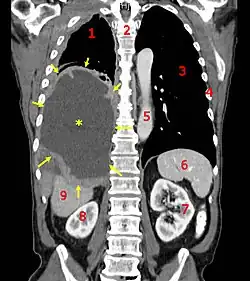

| CT scan showing a left sided mesothelioma with an enlarged mediastinal lymph node | |

Imaging

Diagnosing mesothelioma is often difficult because the symptoms are similar to those of a number of other conditions. Diagnosis begins with a review of the patient's medical history. A history of exposure to asbestos may increase clinical suspicion for mesothelioma. A physical examination is performed, followed by chest X-ray and often lung function tests. The X-ray may reveal pleural thickening commonly seen after asbestos exposure and increases suspicion of mesothelioma.[15] A CT (or CAT) scan or an MRI is usually performed. If a large amount of fluid is present, abnormal cells may be detected by cytopathology if this fluid is aspirated with a syringe.[11] For pleural fluid, this is done by thoracentesis or tube thoracostomy (chest tube); for ascites, with paracentesis or ascitic drain; and for pericardial effusion with pericardiocentesis. While absence of malignant cells on cytology does not completely exclude mesothelioma, it makes it much more unlikely, especially if an alternative diagnosis can be made (e.g., tuberculosis, heart failure). However, with primary pericardial mesothelioma, pericardial fluid may not contain malignant cells and a tissue biopsy is more useful in diagnosis.[11] Using conventional cytology diagnosis of malignant mesothelioma is difficult, but immunohistochemistry has greatly enhanced the accuracy of cytology.